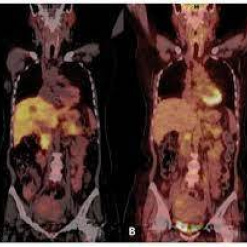

Tomografia por emision de positrones. Unidosis PMSA (PET-CT). 921401 Idime (2024)

IDIME. Instituto de Diagnóstico Médico. Código de Convenio : 8915

INCLUYE UNIDOSIS FDG-18